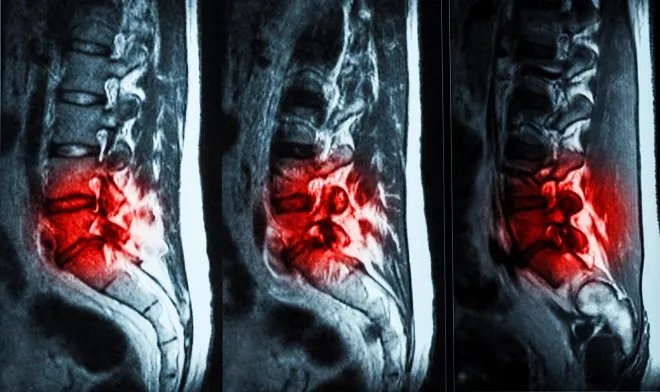

Специально разработанный гидрогель устранит поясничные боли

Американская компания ReGelTec представила собственную разработку гидрогеля Hydrafil, который может навсегда решить проблему поясничной боли. Средство вводится в позвоночник в те места, где диагностированы травмы и трещины поврежденных дисков. В итоге гидрогель частично восстанавливает утраченную амортизацию и снимая боль. На сегодняшний день пациенты 22-69 лет в количестве 20 добровольцев участвуют в испытании средства. Процесс заключается в следующем: нагретый гель становится густым, после чего вводится при помощи шприца в пораженные диски. Средство охлаждается до температуры тела, в результате чего формируется имплантат. По характеристикам он практически не уступает межпозвоночному диску человека. После введения средства пациент полгода еще наблюдается у врача. Испытуемые уже отметили пользу препарата по 10-бальной шкале: снижение болевых ощущений с 7,1 до 2,0, а уменьшение боли, которая мешает заниматься повседневной деятельностью, - с 48 до 6. Больше информации https://regeltec.com/.